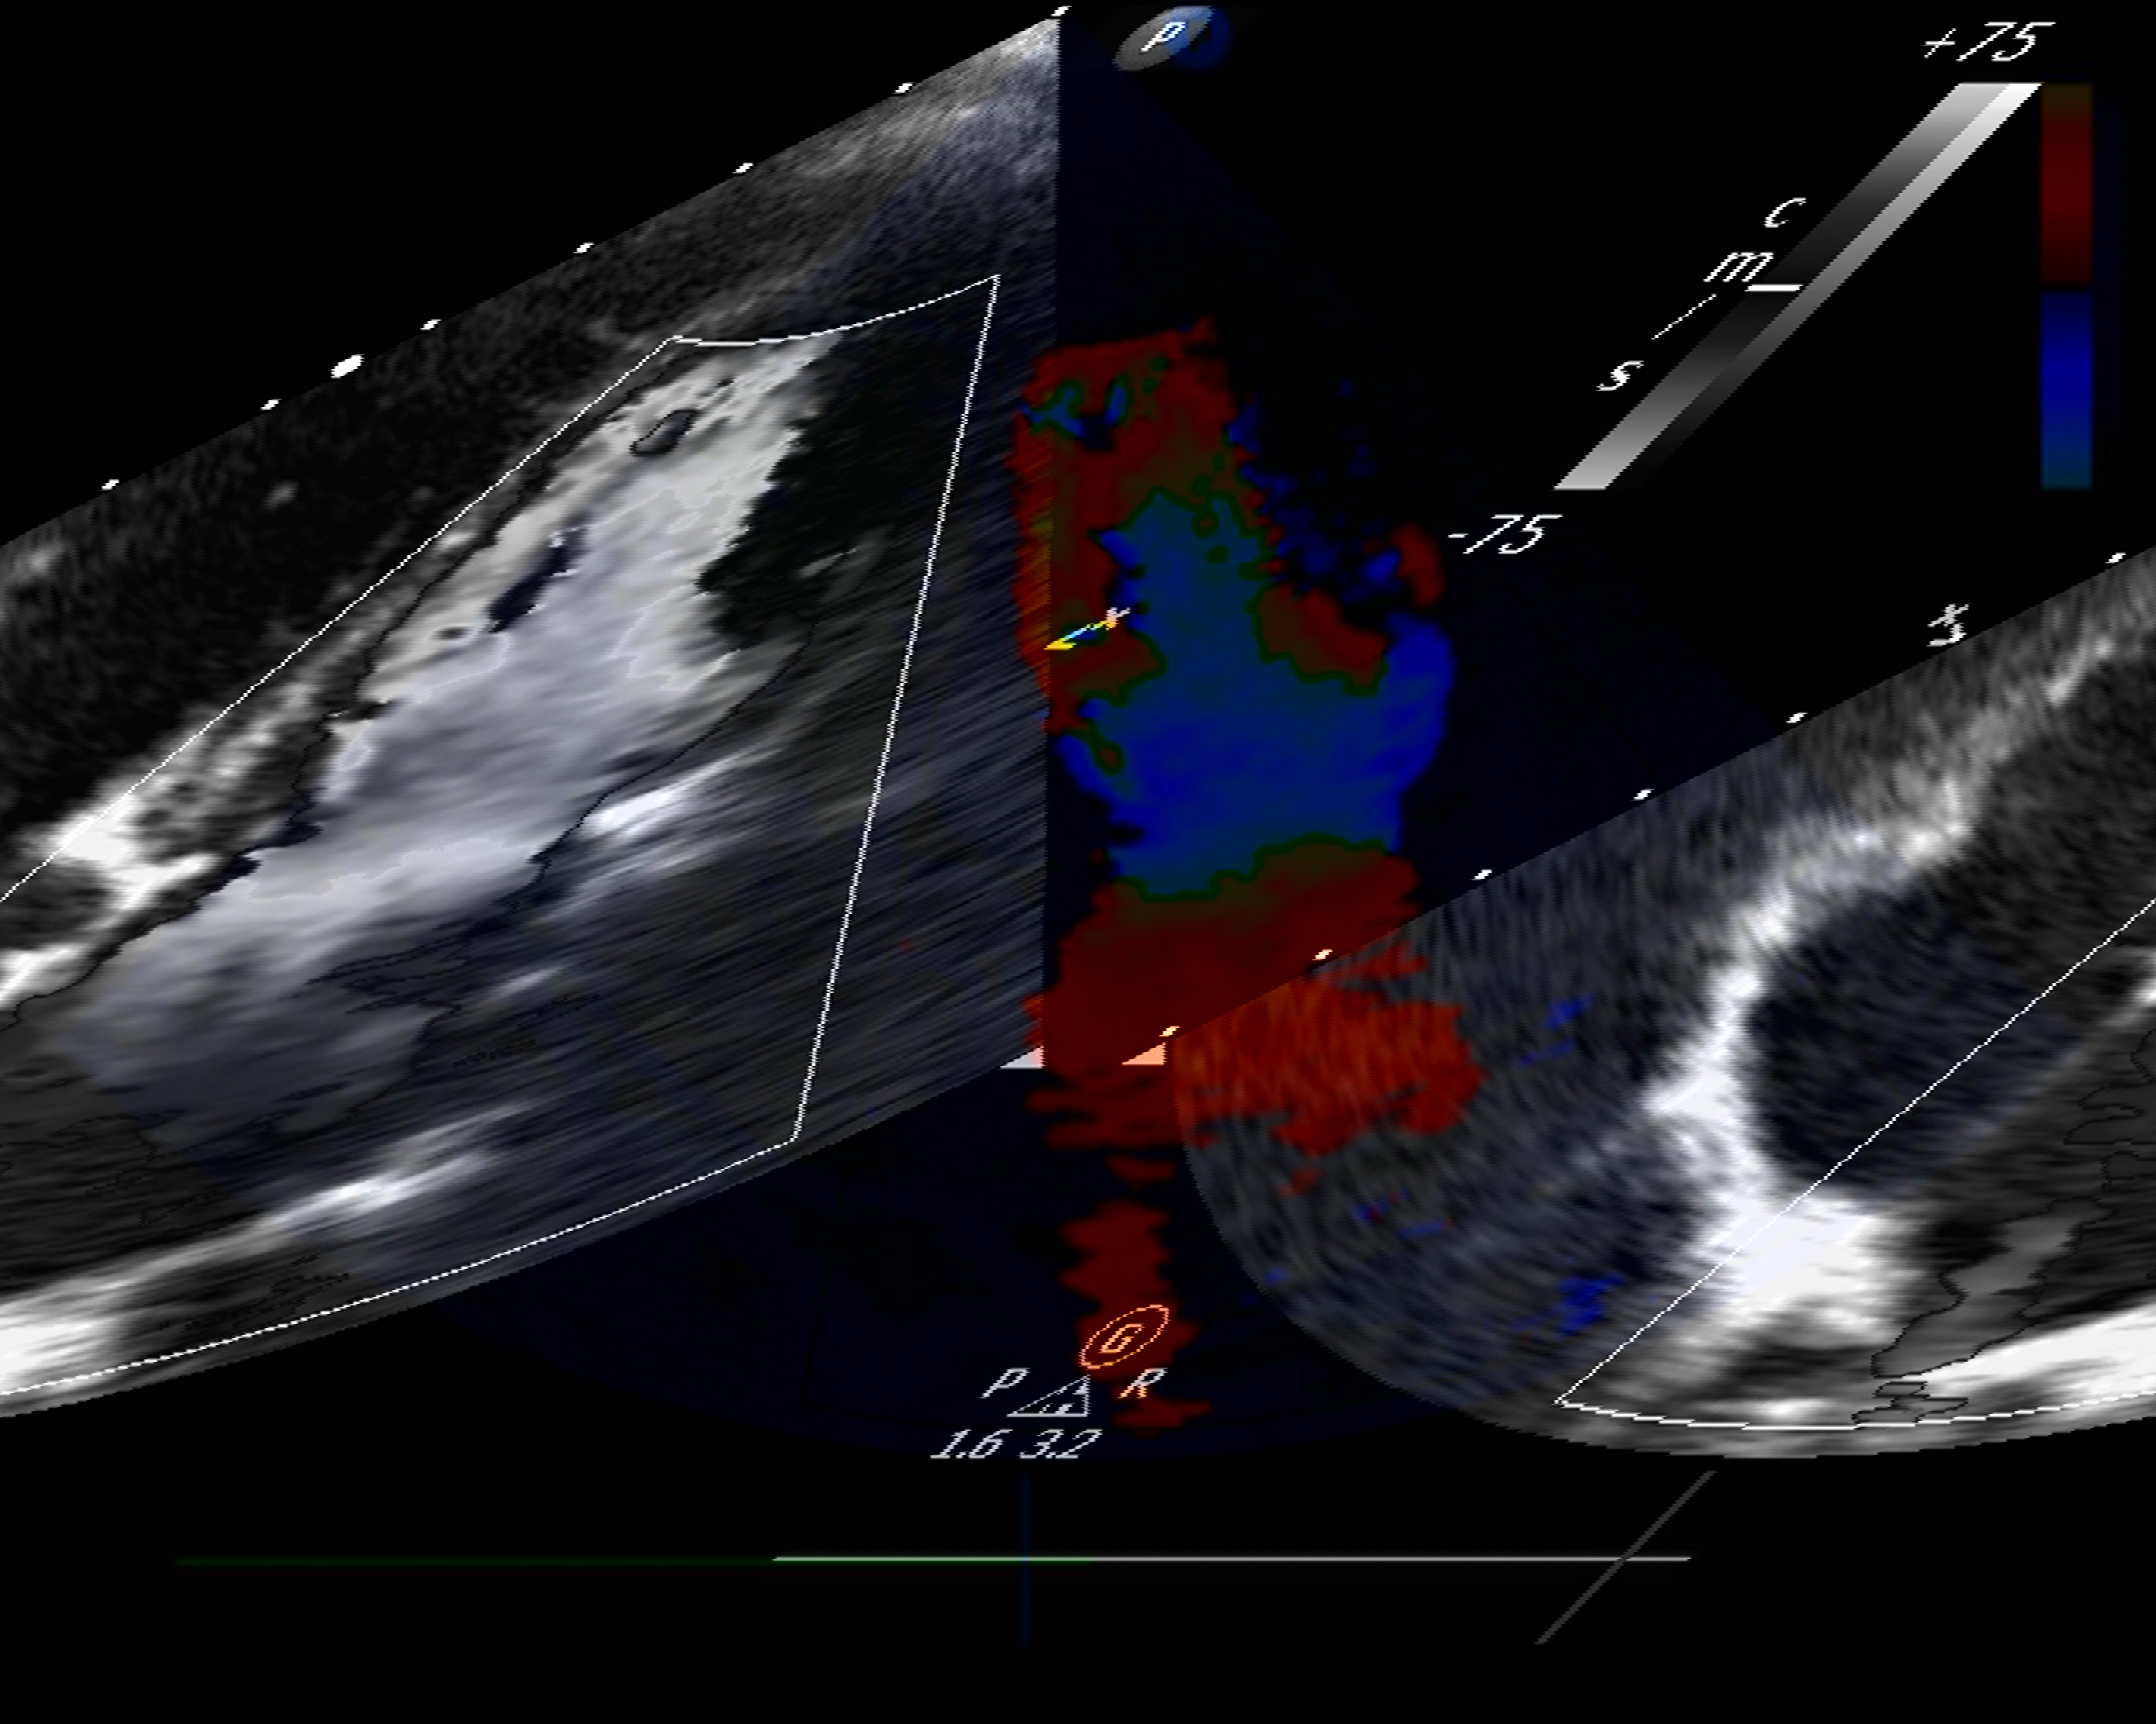

è un esame diagnostico non invasivo e indolore che utilizza una tecnologia a ultrasuoni, l'ecografo, per la visualizzazione e valutazione del cuore.

Durante l'esame, il cardiologo guida una sonda a ultrasuoni sul petto del paziente, che trasmette onde sonore al cuore per ottenere immagini. Le immagini ottenute permettono di valutare le dimensioni del cuore, le valvole cardiache, la forza di pompaggio, il flusso sanguigno nelle 4 camere e i vasi sanguigni vicini al cuore.